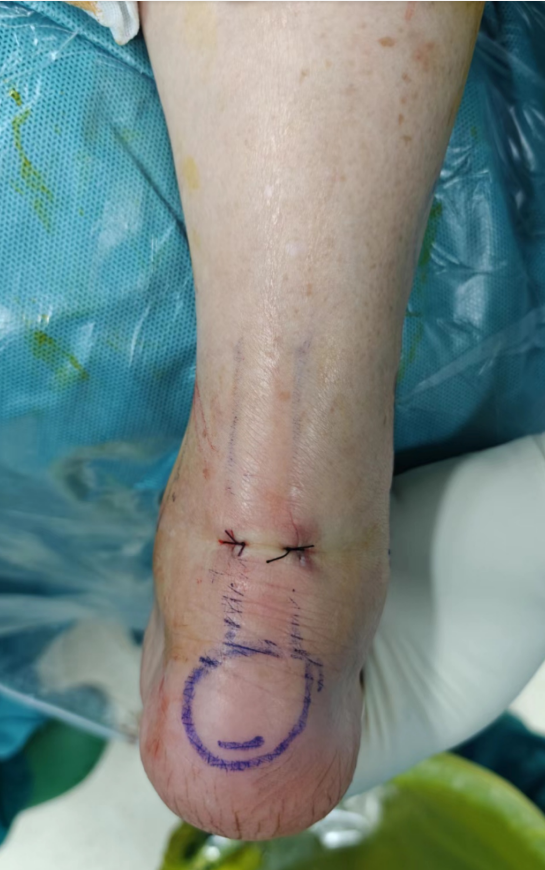

术前标记体位

术中,在患者右踝后部内外侧分别做一约8毫米长的微创小切口,清理增生滑膜、受损软骨,彻底切除所有囊肿,整个手术时间短、出血少,手术顺利完成,术后患者疼痛明显缓解。

术后切口仅8毫米